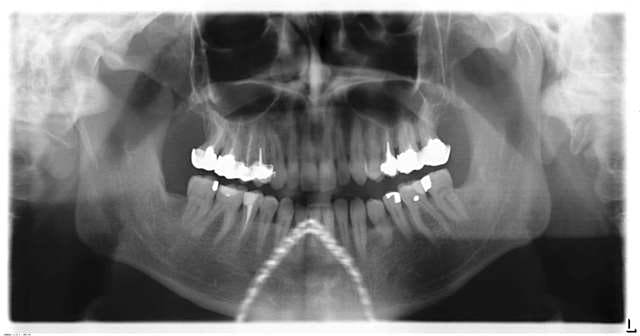

isaïe

08/02/2005 à 12h31

Ce que je vais dire n'est pas conforme à ce que j'utilise comme démarche, il me faut l'impact sur la symétrie des bras, mais d'après le contact sur l45 (qui n'est pas en articulé croisé), et sur p24 il y aurait de fortes chances pour avoir une rétraction à droite, mais c'est à vérifier. Le contact sur l47 est plus délicat pcq on est en croisé (appui ou pas?). Sa latéralité droite doit le mettre très certainement en asymétrie.

Si (hypothèse) l'asymétrie des bras se confirme sur l45 et p24, on pourrait avoir des ennuis dans le côté gauche du tronc( 45, plutôt bas-ventre et 24, 1/2 sup), et si l47 est origine d'asymétrie, voir aussi bas du dos et hanche à gauche ou peut-être genou pcq 46 manque et 47 doit avoir avancé.

Mais si je ne mets pas d'asymétrie en évidence, je ne touche à rien.

Est-ce qu'il n'y a pas de contacts sur le bloc antérieur?

NB. la 45 source d'asymétrie semble statistiquement souvent liée à un problème de métabolisme des sucres (ex. coups de pompe dans la journée, obésité, patients très "sucrés")

Roge, question passionnante, impatient de te lire et de connaître ta façon de faire.